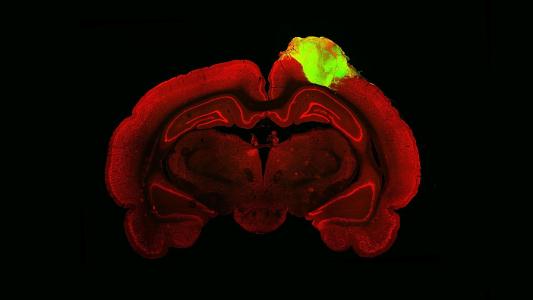

A recent systematic review of neuroimaging studies showed that focused attention meditation is associated with functional changes in several brain regions involved in cognitive control and emotion-related processing. The review also found that more experienced meditators had stronger activation of the brain regions involved in those cognitive and emotional processes, suggesting that the brain benefits improve with more practice.

A regular meditation practice may also stave off age-related thinning of the cerebral cortex, which may help to protect against age-related disease and cognitive impairment.